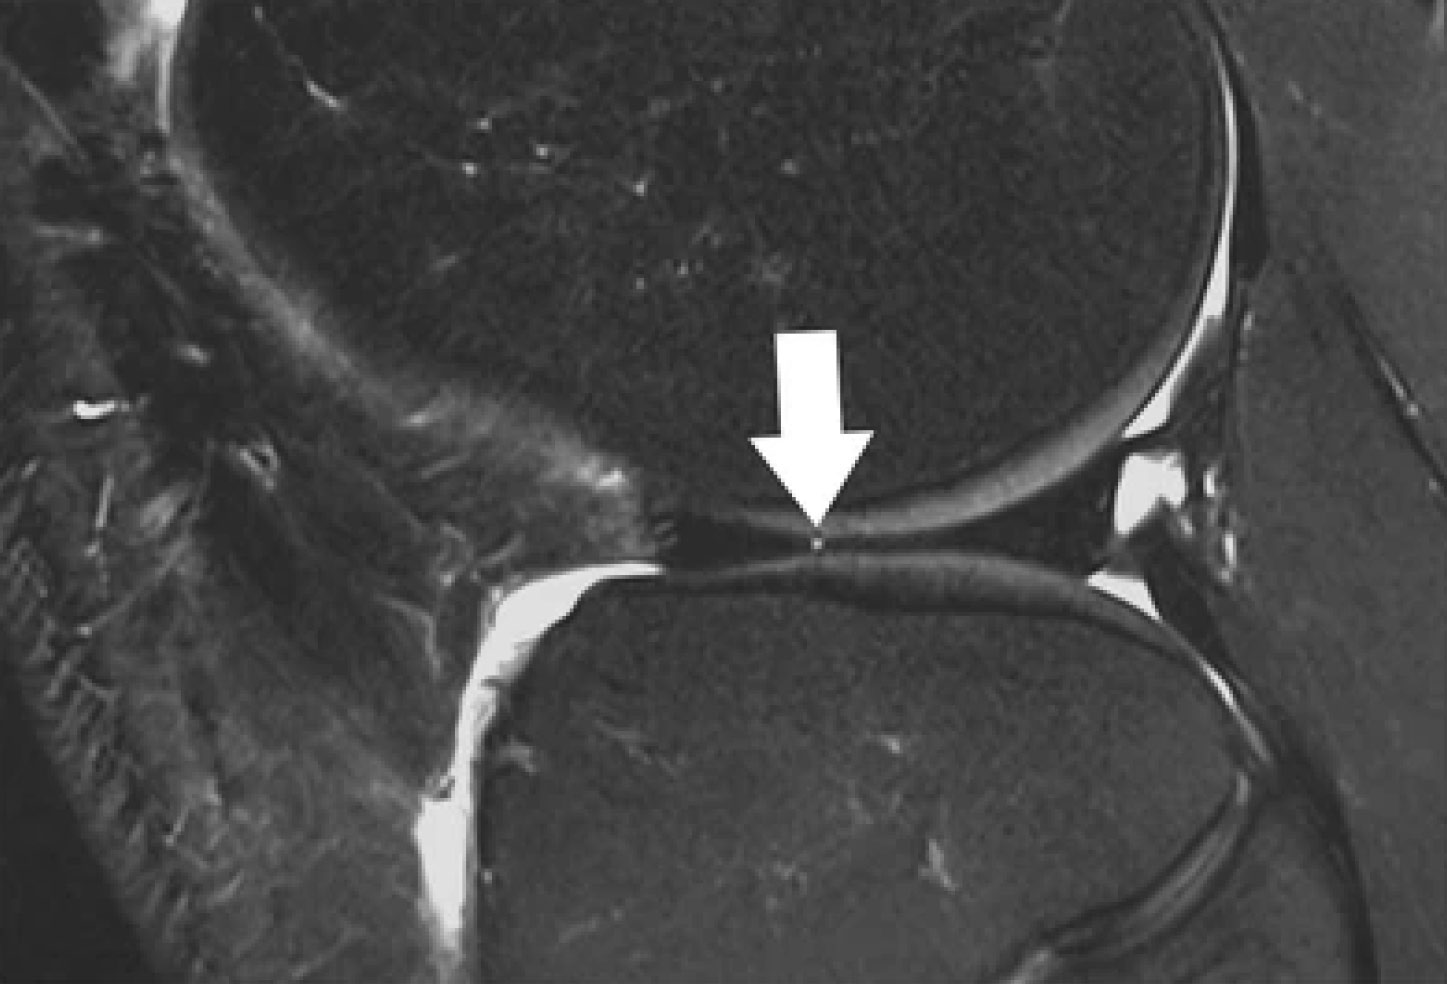

Sagittal T2-weighted, fat-suppressed fast spin echo image of the right knee in a 39-year-old male patient acquired at 3 Tesla (Siemens Healthcare, Erlangen, Germany) using a dedicated 28 channel transmit-receive knee coil shows a small radial tear of the lateral meniscus (arrow). Reprinted from Bolog NV, Andreisek G. Reporting knee meniscal tears: technical aspects, typical pitfalls and how to avoid them. Insights Imaging 2016;7:385–398. https://doi.org/10.1007/s13244-016-0472-y. Use is per Creative Commons Attribution 4.0 International License.